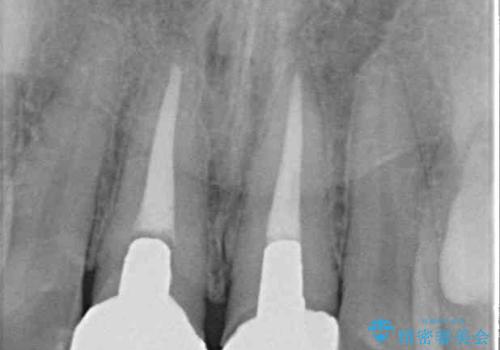

- 前歯のクラウン付近の歯肉が黒く見えることを気にして来院された患者様です。

10年以上前に根管治療を行っており、その際にはラバーダムを使用してしっかりと治療を行っていたとのことで、今回は根管治療は行わずに土台のみを作り替えた上で、オールセラミッククラウンにて補綴治療を行うこととしました。